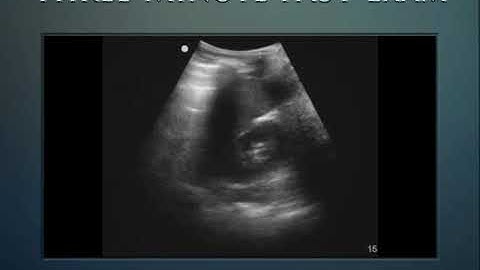

FAST Scan (Focused Assessment with Sonography in Trauma) - STEP by STEP